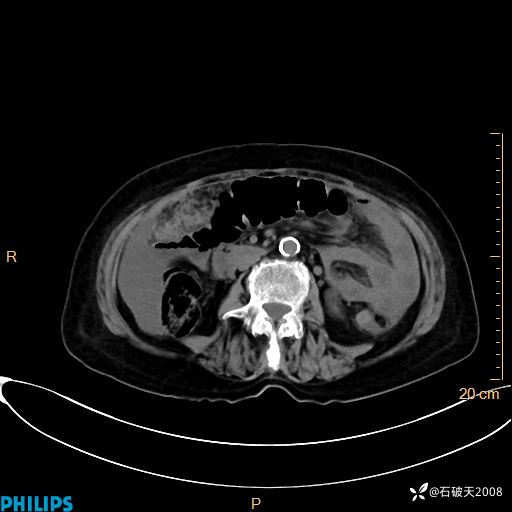

平扫